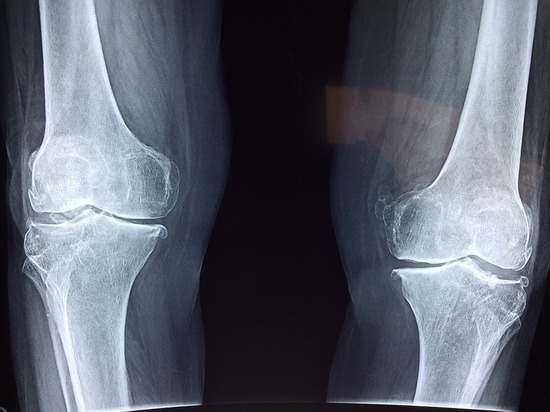

При любой травме человек не может самостоятельно поставить себе диагноз, поэтому даже при обычном ушибе следует обращаться к врачу, чтобы исключить возможные риски. После проведения рентгенологического исследования нередко выясняется, что кости повреждены.

Если вы заметили, что конечность приняла неестественное положение или ее подвижность сильно ограничена, скорее всего, имеют место перелом или вывих. Нужно пойти к доктору, наложить гипс или вправить сустав. В тяжелых случаях может потребоваться и хирургическая операция (открытая репозиция).